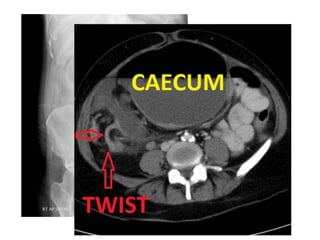

Large bowel obstruction

• volvulus

• Caecal volvulus (1-3%)

• Sigmoid volvulus (3-8%)

Large bowel obstruction •Epidemiology • 20% of all bowel obstructions • Clinical presentation • Presentation is typically with abdominal pain, distension and absolute constipation; eventually  sign of perforation • Aetiology • Malignancy • Colorectal carcinoma  (most common, 50-60%) • pelvic tumours; direct spread or metastatic disease • Colonic diverticulitis • volvulus • Caecal volvulus (1-3%) • Sigmoid volvulus (3-8%) • ischaemic stricture  • faecal impaction/faecoloma (most common cause in debilitated elderly)